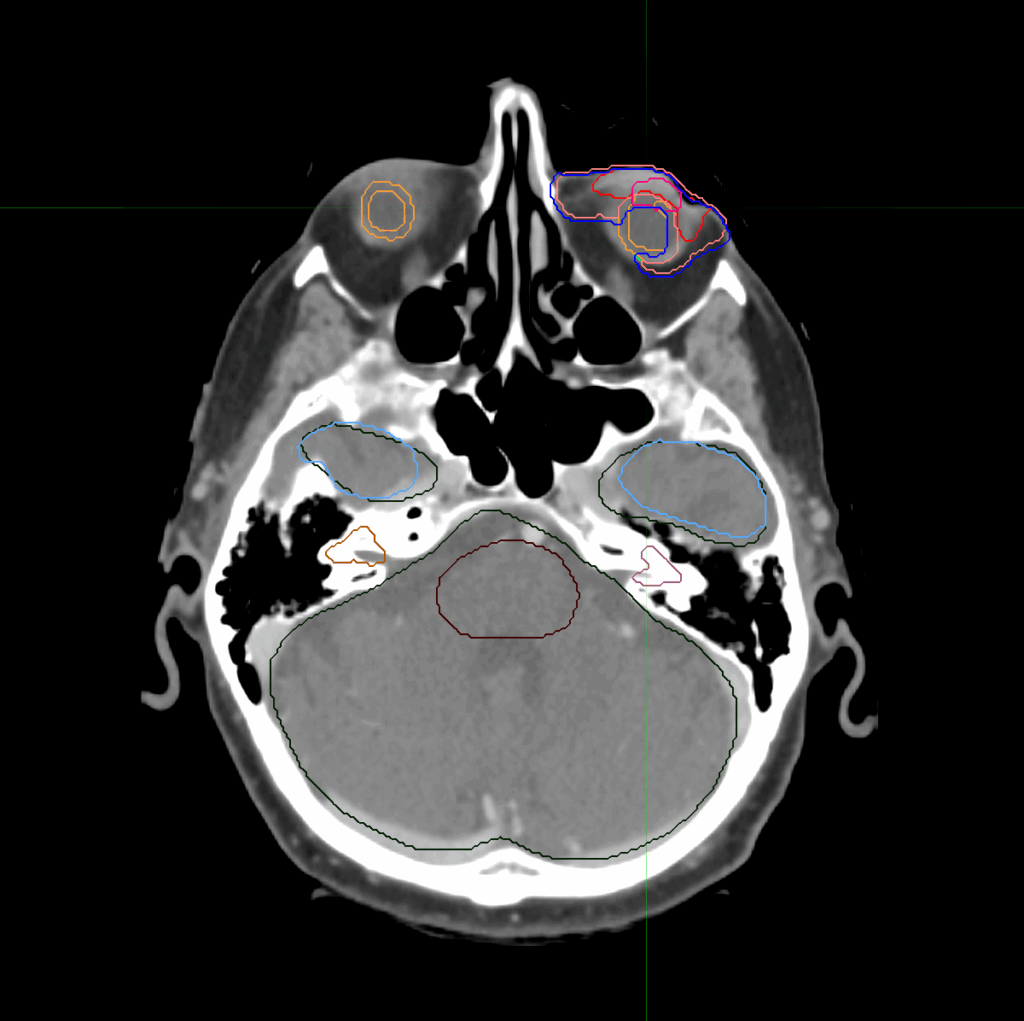

Planning CT Images